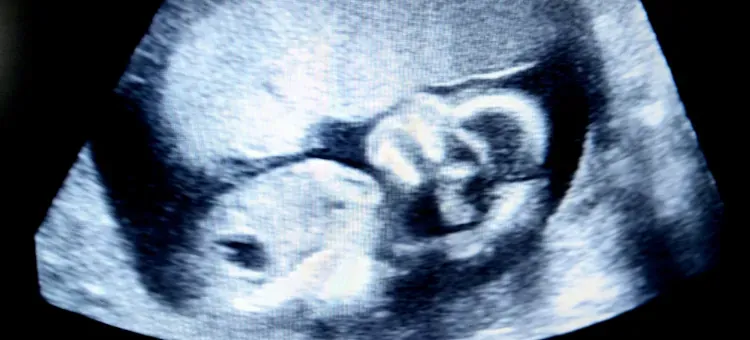

W 24. tygodniu ciąży, kiedy patrzę na badania USG, zawsze z podziwem obserwuję, jak bardzo dziecko jest już ukształtowane. To już nie jest tylko zbiór komórek, ale w pełni uformowana, choć oczywiście miniaturowa, istota ludzka. W tym momencie maluszek mierzy około 30 centymetrów długości, licząc od głowy do stóp, a jego waga oscyluje w granicach 600 do nawet 700 gramów. Aby łatwiej było sobie to wyobrazić, często porównuję jego rozmiar do sporej kolby kukurydzy. To naprawdę robi wrażenie, prawda?

Kiedy przyglądamy się bliżej, wygląd zewnętrzny dziecka w 24. tygodniu ciąży jest już coraz bardziej proporcjonalny. Ciało nabiera ludzkich kształtów, choć wciąż jest bardzo delikatne. Skóra maluszka jest niezwykle cienka, delikatna i jeszcze mocno pomarszczona. Ma ona czerwonawy odcień, co jest zupełnie normalne na tym etapie. Dlaczego? Ponieważ przez cienką skórę prześwitują naczynia krwionośne, a pod nią nie ma jeszcze wystarczającej ilości tkanki tłuszczowej, aby nadać jej pełniejszy wygląd. Co ciekawe, rysy twarzy są już w pełni ukształtowane możemy dostrzec brwi, rzęsy, a nawet delikatne włoski na głowie. Często są one jeszcze bardzo jasne, pozbawione pigmentu, ale ich obecność to kolejny krok w rozwoju.